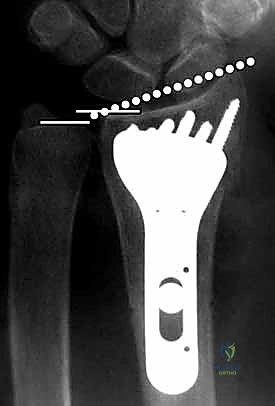

يعتمد الدكتور محمد هطيف على أحدث التقنيات التشخيصية، حيث يبدأ بـ الأشعة السينية (X-rays) في وضعيات متعددة. وفي حالات الكسور المعقدة التي تمتد إلى داخل المفصل، يتم إجراء تصوير مقطعي محوسب (CT Scan) لبناء صورة ثلاثية الأبعاد للكسر، مما يساعد في التخطيط الجراحي الدقيق.

4. وضع الصفيحة والتثبيت المؤقت

يتم اختيار صفيحة تيتانيوم مصممة تشريحياً لتلائم انحناء الكعبرة. توضع الصفيحة على العظم وتُثبت مؤقتاً بأسلاك معدنية دقيقة (K-wires).

5. حفر العظم ووضع المسامير

يتم حفر ثقوب في العظم عبر فتحات الصفيحة، ثم تُقاس المسافات بدقة لإدخال مسامير القفل (Locking Screws) في الجزء البعيد (قرب المفصل) ومسامير قشرية في الجزء القريب (في ساق العظم).

6. الفحص النهائي والإغلاق

يتم إجراء فحص أخير بالأشعة للتأكد من المحاذاة المثالية للكسر وأطوال المسامير (لضمان عدم بروزها واحتكاكها بالأوتار الخلفية). بعد ذلك، يتم خياطة الأنسجة والجلد بخيوط تجميلية ووضع ضمادة معقمة.